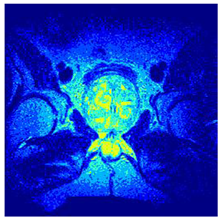

In this subsection, we will discuss the experiment designed to evaluate the performance of EO with cross-entropy for the segmentation of prostate MRI images. To this end, we use a group of reference images formed by a set of six prostate MRI images; see Figure 4. All the images from the group were extracted from the Ferenc Jolesz National Center for Image-Guided Therapy, Harvard Medical School, or Brigham Health Hospital datasets with no additional preprocessing [50]. Prostate MRI images are primarily used for disease diagnosis or to establish treatment for prostate-related diseases such as prostatitis, benign prostatic hyperplasia (BPH), and prostate cancer, among other diseases or medical conditions. In the context of this article, the images were used to test the efficiency of the equilibrium optimizing algorithm and compare it with the other six chosen algorithms. The segmentation of MRIs is carried out over four different thresholds levels: = 3, 4, 5, and 8. Due to the nature of the images, there was a limited number of different tissues in the images; thus, there was no point in evaluating a larger number of .

Figure 4.

Eleven transaxial-cut prostate MRI images. This figure presents a set of eleven transaxial-cut magnetic resonance (MR) images of the prostate. These images serve as the input dataset for evaluating the segmentation performance of the proposed algorithm.

Table 5 presents the segmentation of the MRIs using EO for a qualitative inspection. From Figure 5, it is clear that two lumps in the prostate have been highlighted by the thresholding process. Prostatic MRIs present noisy conditions, which makes it difficult to visualize the thresholding with the naked eye, so in Figure 5 we present the thresholded image as well as the histogram with the values of the thresholds generated by the EO. It can be observed in the histogram that the thresholds present an adequate distribution, even though this particular image has impulsive noise and a simple shape. Our findings indicate that four thresholds are typically sufficient for this application, which corresponds to identifying five different tissue types in the image. A smaller threshold value may result in a lack of sufficient contrast to highlight relevant anatomical structures, such as the prostate capsule. In contrast, a higher number of thresholds may lead to the incorrect differentiation of anatomical regions that should be connected.

Table 5.

Segmentation of transaxial-cut prostate MRI images Using EO and cross-entropy. This table presents the segmentation results of transaxial-cut prostate MRI images using the equilibrium optimizer (EO) and cross-entropy. Each row corresponds to a distinct MRI image, while the columns nt represent the number of thresholds applied during segmentation. The results illustrate the performance of the EO algorithm across different threshold levels for each image.